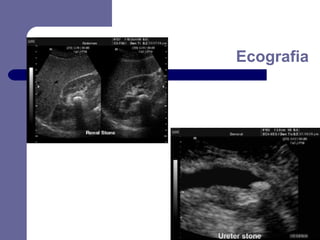

Ecografia

 Melhor

–

presença de litíase

repercussão mecânica aguda sobre o excretor

 Pode

método para identificar:

mostrar:

repercussão crónica

existência de infecção do parênquima, do excretor

ou peri-renal

presença de factores predisponentes

 Limitações

identificação química provável dos cálculos

avaliação do tamanho e forma dos cálculos

visualização de cálculos do ureter médio

correcta avaliação da massa litiásica

avaliação da função renal